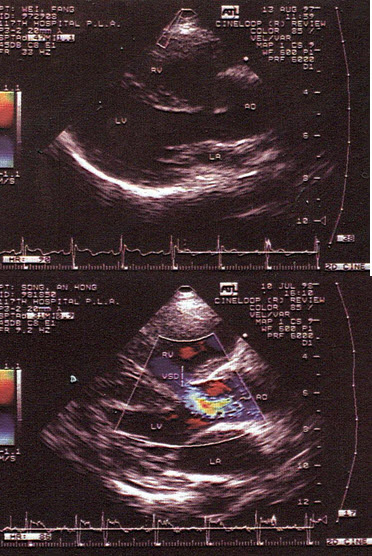

55、单项选择题

孕8周时感冒,产前超声检查胎儿心脏见图,最可能的诊断是()

A.单心室

B.房间隔缺损

C.室间隔缺损

D.大动脉转位

E.正常心脏

C.M型

D.音频数据

E.二维超声

99、名词解释 CPA

100、单项选择题 声阻抗产生与下列哪项最有关系()

A.声束宽度和交界面曲度

B.振荡频率和晶片的体积

C.超声在组织中的声速和组织密度

D.声波能量和组织敏感度